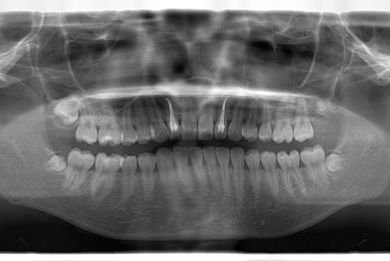

性別/年齢 女性 / 23歳

主訴 虫歯の治療をしたい。

治療方針 セラミック治療にて審美的回復を行う。

治療内容 オールセラミッククラウン4本(オールセラミック用土台2本)

治療部位

2 1 1 2

総治療費 553,350円

治療期間 4ヶ月